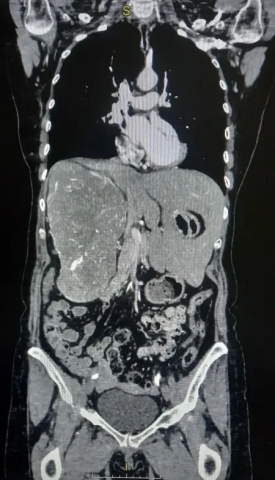

В Волгоградском областном онкологическом диспансере хирурги провели уникальную операцию, столкнувшись с редким случаем: гигантское новообразование почки вытеснило жизненно важные органы. Опухоль заполнила правую половину брюшной полости так, что печень сместилась влево.

Пациентка долгое время жаловалась на боли в пояснице и тяжесть в животе. Компьютерная томография с контрастированием показала, что опухоль почти полностью заняла правую половину брюшной полости. Правая почка почти не функционировала, как показало динамическое сканирование. Размеры опухоли составляли 16,5х11,5х21,1 см.